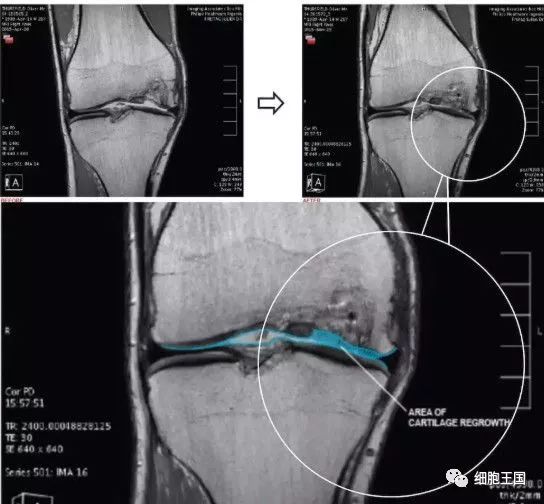

墨尔本干细胞治疗中心利用患者自身的间充质干细胞注入膝关节治疗膝关节损伤的临床研究是全球范围都较为知名的一项临床试验,这个试验共涉及70名患者,分为30名一组进行对照。最终结果显示,大部分参与试验的患者膝关节功能有了很大的改善:三分之二的患者膝盖疼痛程度和活动受限程度减少了一半,并且保持了一年以上。

另一项脂肪干细胞治疗膝骨性关节炎的临床疗效及二期关节镜检查。研究人员分别向30例平均年龄为65岁老年患者的关节腔内注射平均值为4.0×106干细胞,随后进行了2年的随访。十六例患者在此期间进行了第二次关节镜检查,几乎所有患者均有明显改善,其中87.5%的老年患者改善或维持软骨状态至少2年。而且,没有一个病人接受过在这2年期间进行全膝关节置换术。在一部来自Youtube上的视频中,医生采集患者自身外周血中的干细胞,联合PRP(富血小板血浆)治疗关节病,患者自述这种疗法有效缓解了疼痛,提高了生活质量。